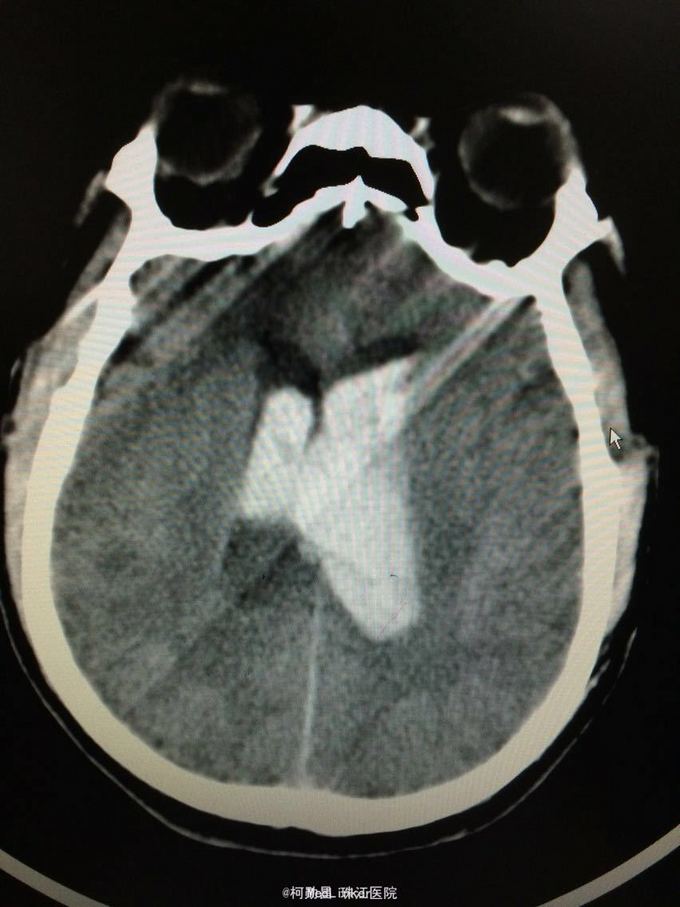

主诉:突发意识障碍4小时 病史:患者57岁男性,入院前一天晚上突发意识不清,伴呕吐胃内容物多次,无肢体抽搐等,随即由家人呼叫120送至我院,急诊行头颅CT提示左侧基底节区出血破入脑室。既往高血压病史10多年

查体:神志不清,双侧瞳孔散大,对光反射消失,四肢肌张力正常,肌力无法检查 辅助检查:头颅CT提示左侧基底节区出血破入脑室

诊断:左侧基底节区出血并破入脑室 处理:急诊行侧脑室钻孔外引流术,术后并予积极抢救,最终抢救无效死亡

随访:患者最终死亡。 讨论:该患者属于典型的高血压性脑出血,且出血量多,预后不良。壳核和丘脑是高血压性脑出血的两个最常见部位。典型可见三偏体征(病灶对侧偏瘫、偏身感觉缺失和偏盲等),大量出血可出现意识障碍,也可穿破脑组织进入脑室,出现血性CSF,直接穿破皮质者不常见。